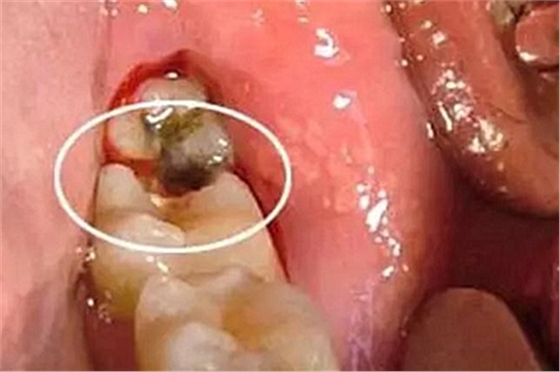

8、根分叉病變的檢查

根分叉病變是指牙周炎發(fā)展到較重的程度后,病變累及多根牙的根分叉區(qū),它可發(fā)生于任何類型的牙周炎。下頜第一磨牙患病率最高,上頜雙尖牙患病率最低。發(fā)生率隨年齡增大而上升。

操作方法:

用普通的彎探針或專門設計的Nabers探針探查多根牙的分叉區(qū)。檢查上頜磨牙時,先探查頰側中央處的根分叉區(qū),再從腭側分別探查近中和遠中的根分叉區(qū),但有的會有變異,需從頰側探入;檢查下頜磨牙時,從頰側和舌側中央處分別探查根分叉區(qū)。探查的內容應包括:探針能否水平方向探入分叉區(qū),水平探入的深度,分叉的大小,有無釉質突起,根柱的長度,根分叉區(qū)是否有牙齦覆蓋,注意檢查根分叉區(qū)是否暴露。

牙周袋和骨吸收波及根分叉區(qū),可從臨床上探查到。主要根據(jù)探診和X線片來判斷病變的程度。Glickman將其分為四度,此分類法有利于指導治療和判斷預后。